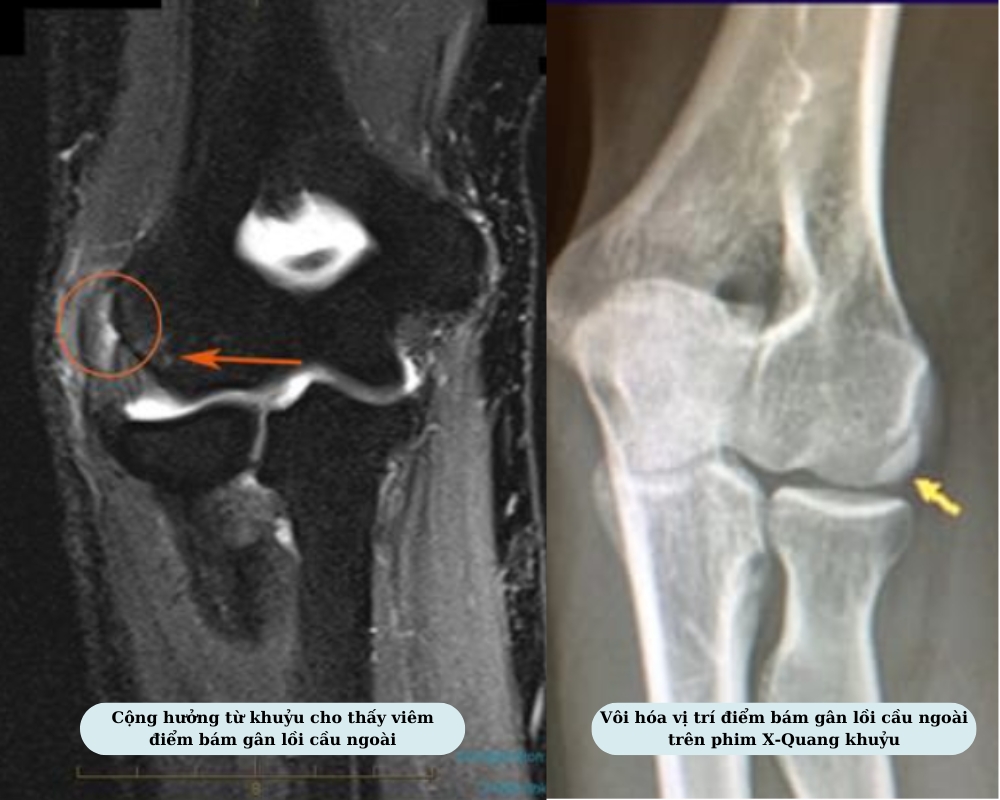

- Chụp cộng hưởng từ: Phát hiện thoái hóa cột sống cổ/ thắt lưng, thoát vị đĩa đệm, nhờ vậy, xác định chính xác nguyên nhân đau khuỷu tay.

- Chụp X-quang: Phương pháp được dùng để kiểm tra tình trạng viêm khớp khuỷu tay, thấy được hình ảnh phì đại hoặc mảnh xương ở lồi cầu ngoài.